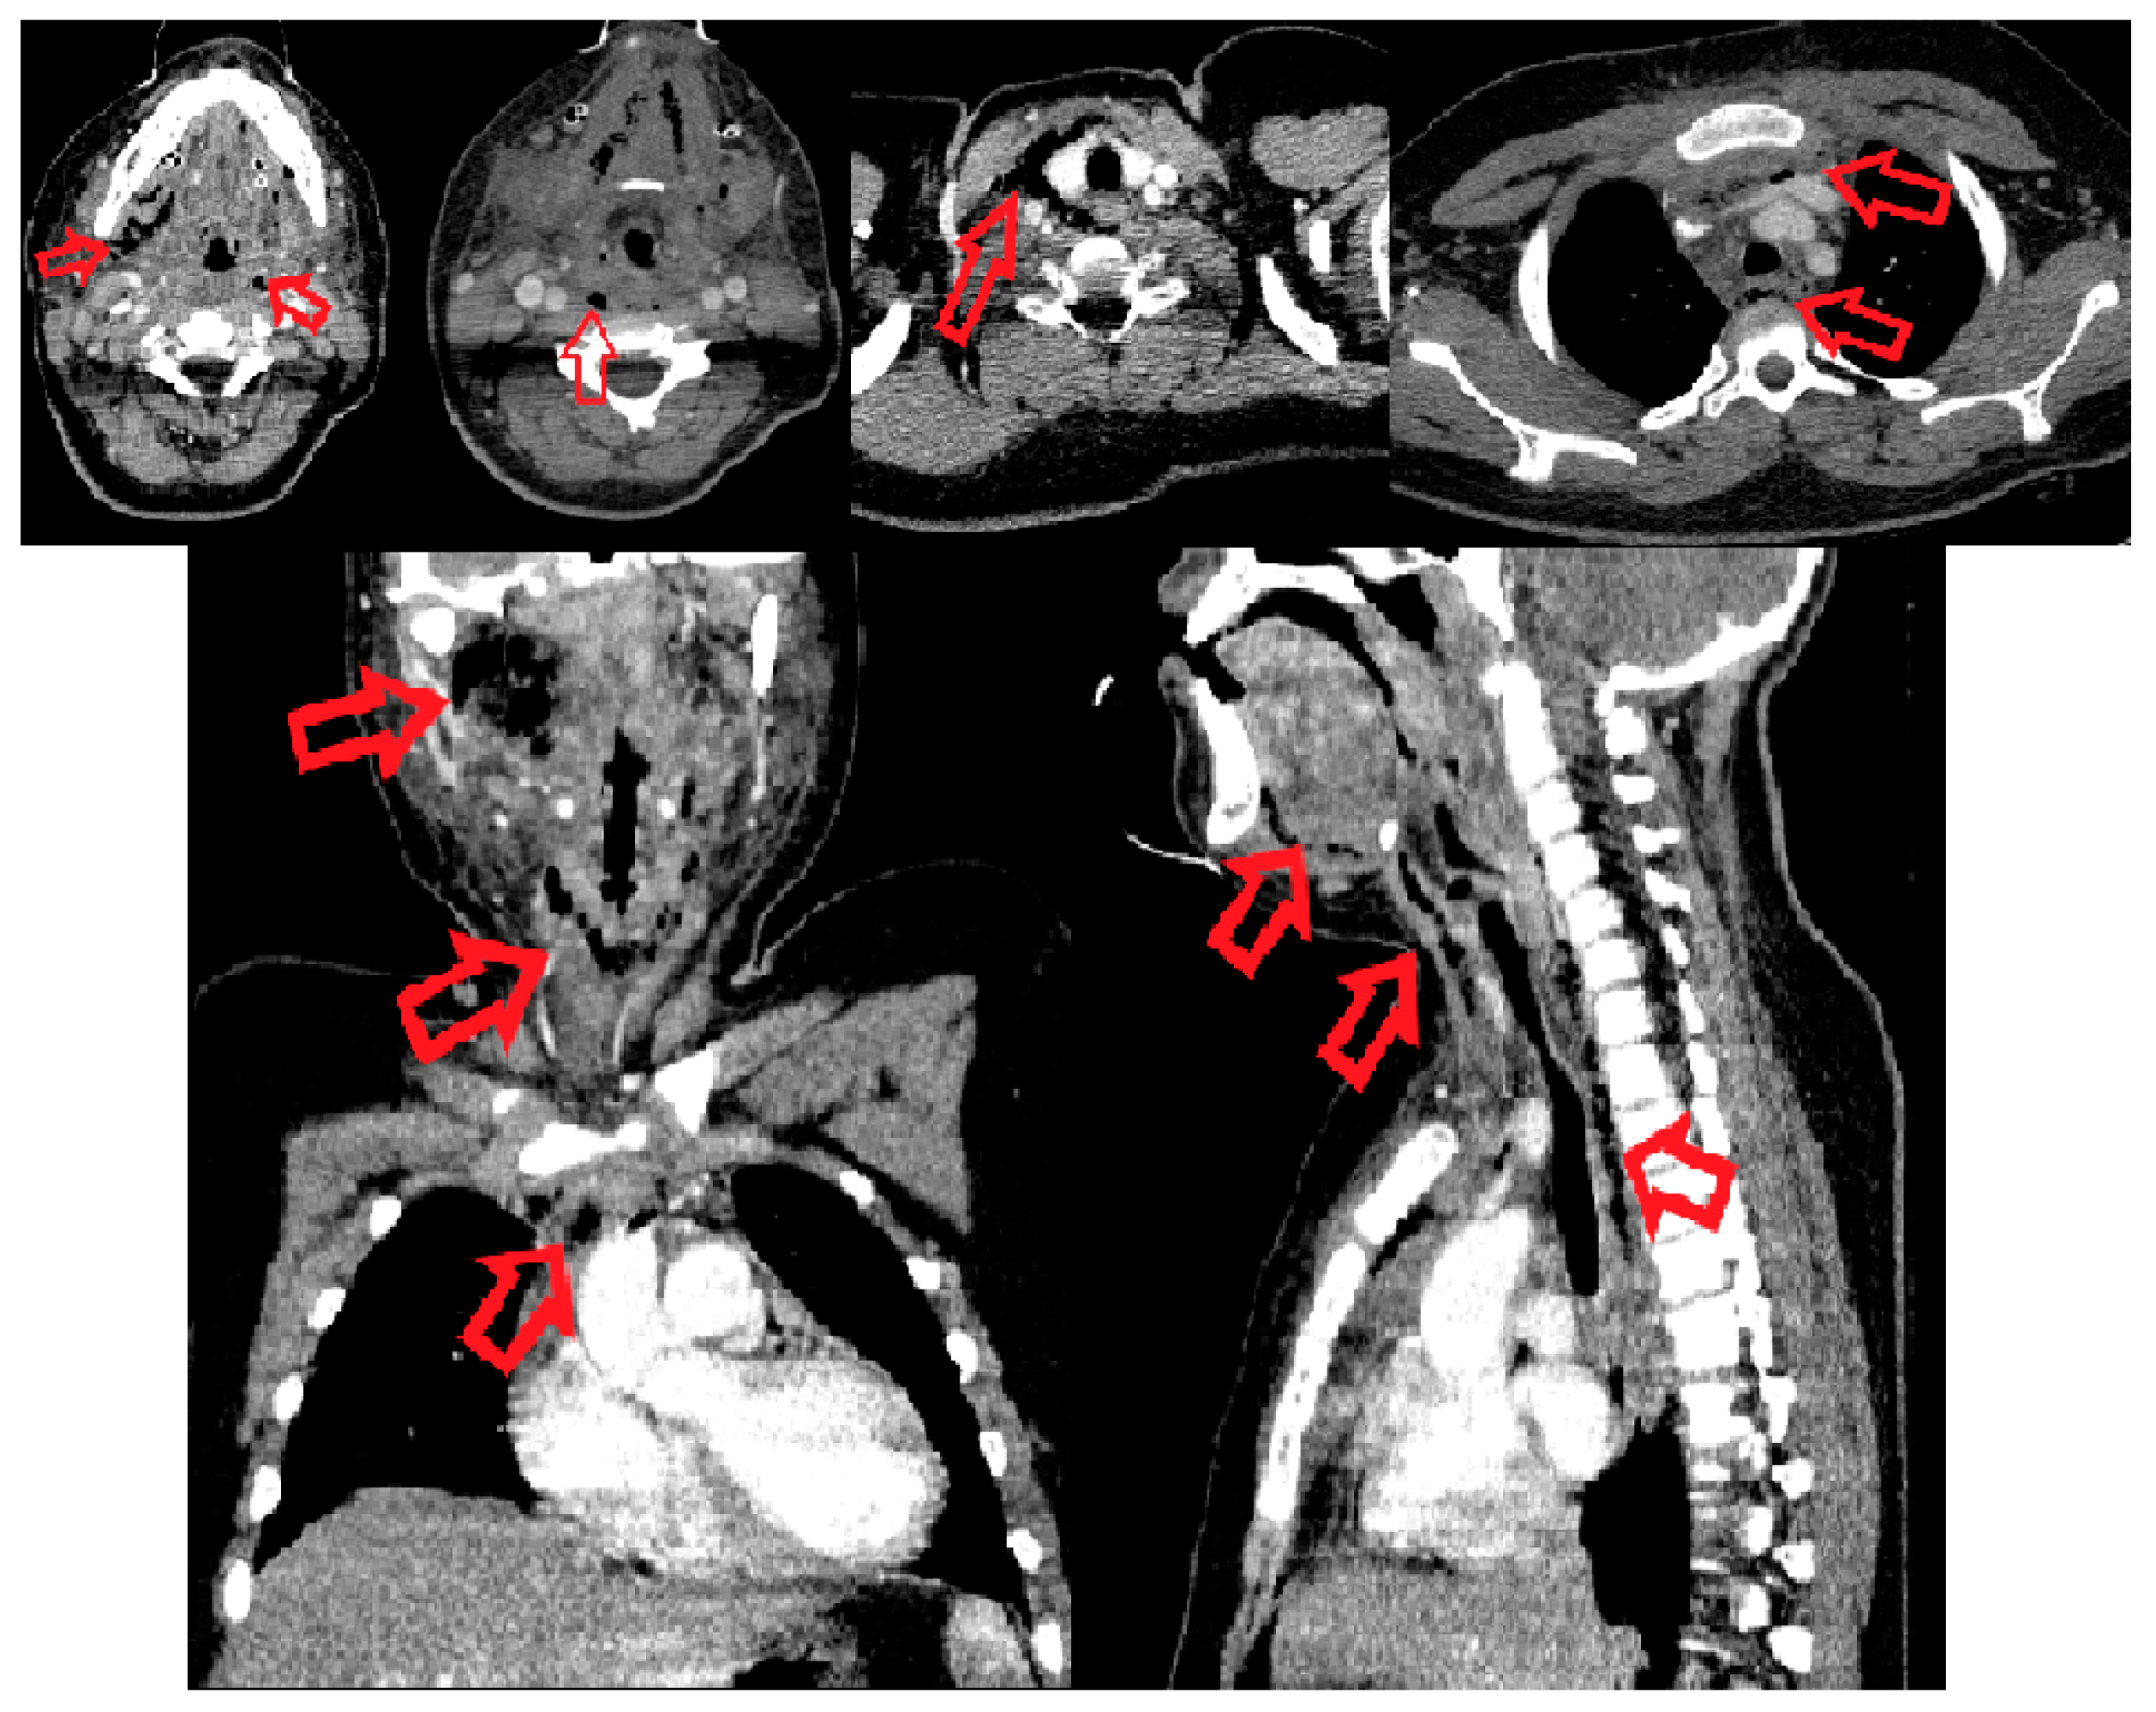

On the same day, surgical reintervention was performed by joining and widening the bilateral subangulomandibular incisions, and the submandibular, sublingual, the base of the tongue and bilateral infratemporal fossae were opened and explored by means of blunt dissection. Necrotic secretions and fetid-smelling gases were eliminated. A right curved horizontal laterocervical incision was performed to open the vascular space of the common carotid artery and its branches, the internal jugular vein, the paratracheal space (anterior, posterior and right lateral), reaching also to the right prevertebral space. Drainage of the anterior superior mediastinum was performed, entering from the neck incision, dissecting bilaterally along the anterior border of the SCM muscle, incising the superficial cervical fascia and both layers of the deep cervical fascia above the jugular notch. Keeping contact with the internal surface of the sternal manubrium, blunt dissection was made, approximately 12 cm long, caudally. Necrotic secretions were evacuated, and drainage was achieved with silicone tube. (Figure 2). All the anatomic spaces described previously were meshed. Postoperative CT scan was made in order to evaluate the drainage of all anatomical spaces involved (Figure 2). After the surgery, the treatment continued in the children’s Intensive Care Unit, and the patient remained sedated, intubated and mechanically ventilated. The wound dressings were changed three time/day. During daily wound care surgical debridement, necrotic fascia mainly around the great vessels of the neck were excised (with skeletonization of the common carotid artery and its internal and external branches, internal jugular vein, right next to the right brachiocephalic artery). Due to the complex local treatment, local evolution was slowly favorable.

Figure 2. CT scan: Postoperative reevaluation of the involved anatomical spaces. Red arrows point to the drainage tubes inserted into the infratemporal region bilaterally, submandibular space bilateral, floor of the mouth, parapharyngeal and retropharyngeal space and anterior mediastinum.